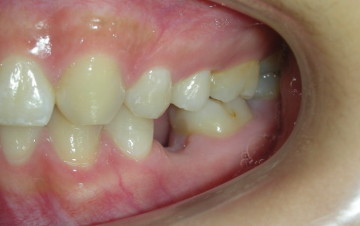

患者許小姐,左下第二小臼齒,因為深度蛀牙,因而牙齒被拔除(圖一、圖二、圖三),患者由於是一位高二學生,深怕缺牙久了若不處理,鄰牙可能倒過來(圖四),但若以傳統假牙修復,還需再磨完整的自然牙(圖五),經轉診至本診所尋求人工植牙。

圖一 |